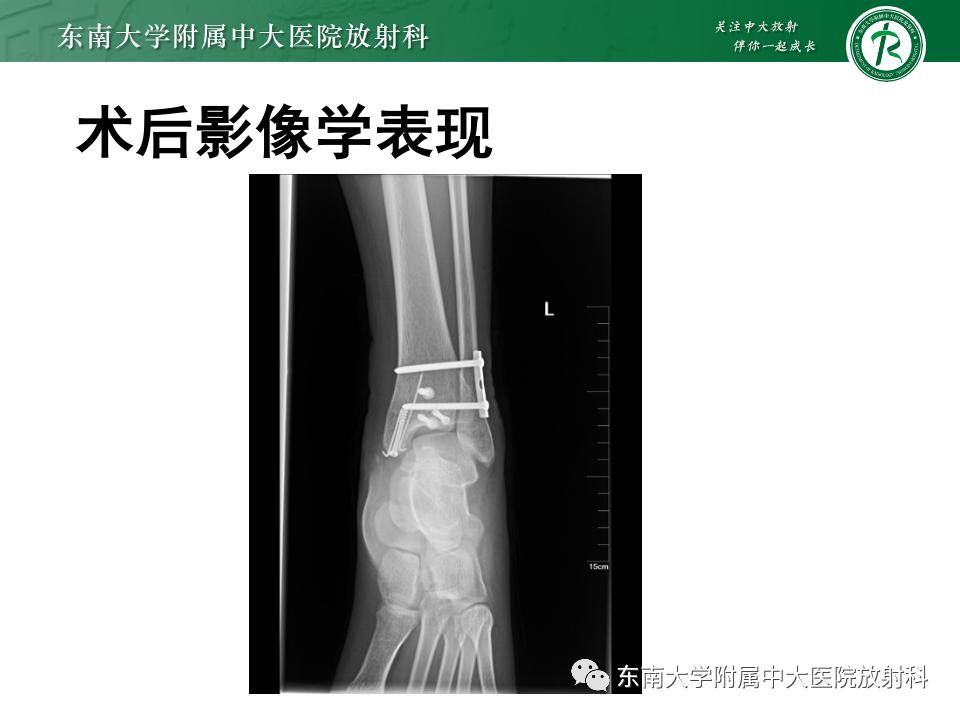

影像学表现

左腓骨下段骨折伴下胫腓联合分离,好文分享深度揭秘